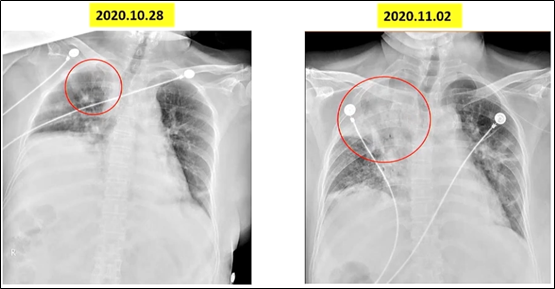

骨髓穿刺结果提示患者骨髓增生活跃,红系增生为主,可见病态造血。血液科会诊意见:不排除骨髓增生异常综合征的可能。痰培养和血培养均回报肺炎克雷伯菌,对哌拉西林他唑巴坦敏感,但患者病情依然恶化。复查胸部X线片可见右上肺大片实变影(图1)。

图1 患者胸部X线片